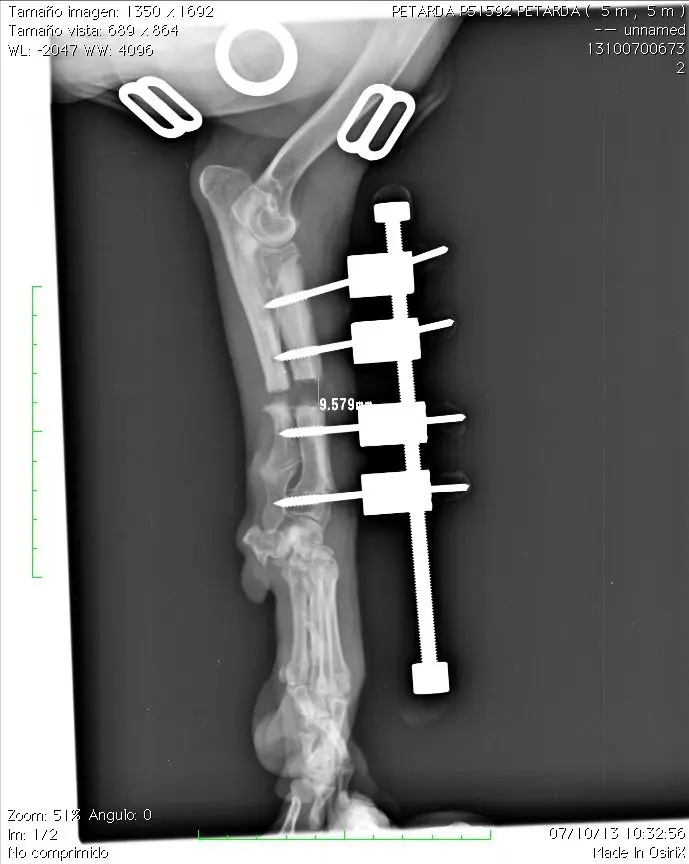

Caso 1

Petarda, beagle, hembra, 5 meses.

Cierre prematuro epífisis distal del radio. Incongruencia codo. Poca desviación de la extremidad

Diferencia de longitud entre ambas extremidades anteriores: 15 mm

Aspecto final del paciente con el elongador “in situ”. Debe planificarse cuidadosamente que disponemos del suficiente espacio en la barra distractora proximal y distal que nos permita la elongación a realizar. La barra proximal puede cortarse con una cizalla si es excesivamente larga y se clava en la piel del paciente. La parte distal no debería cortarse ya que en caso de hacerlo, dificulta la inserción de la arandela grafilada. No debe sobrepasar el nivel de la articulación metacarpo-falangiana

Deben realizarse radiografías semanalmente para comprobar que la distracción es efectiva